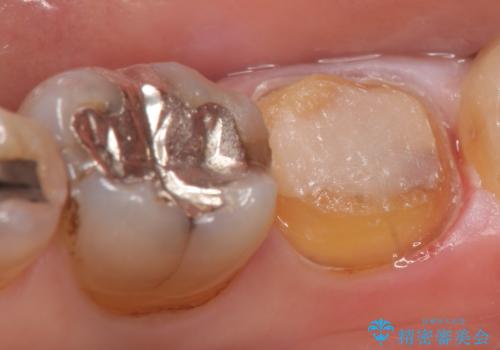

- 右下7の銀歯が外れてしまった方の症例です。

古い樹脂やカリエスを除去後、形を整え、オールセラミッククラウンによる補綴を行いました。